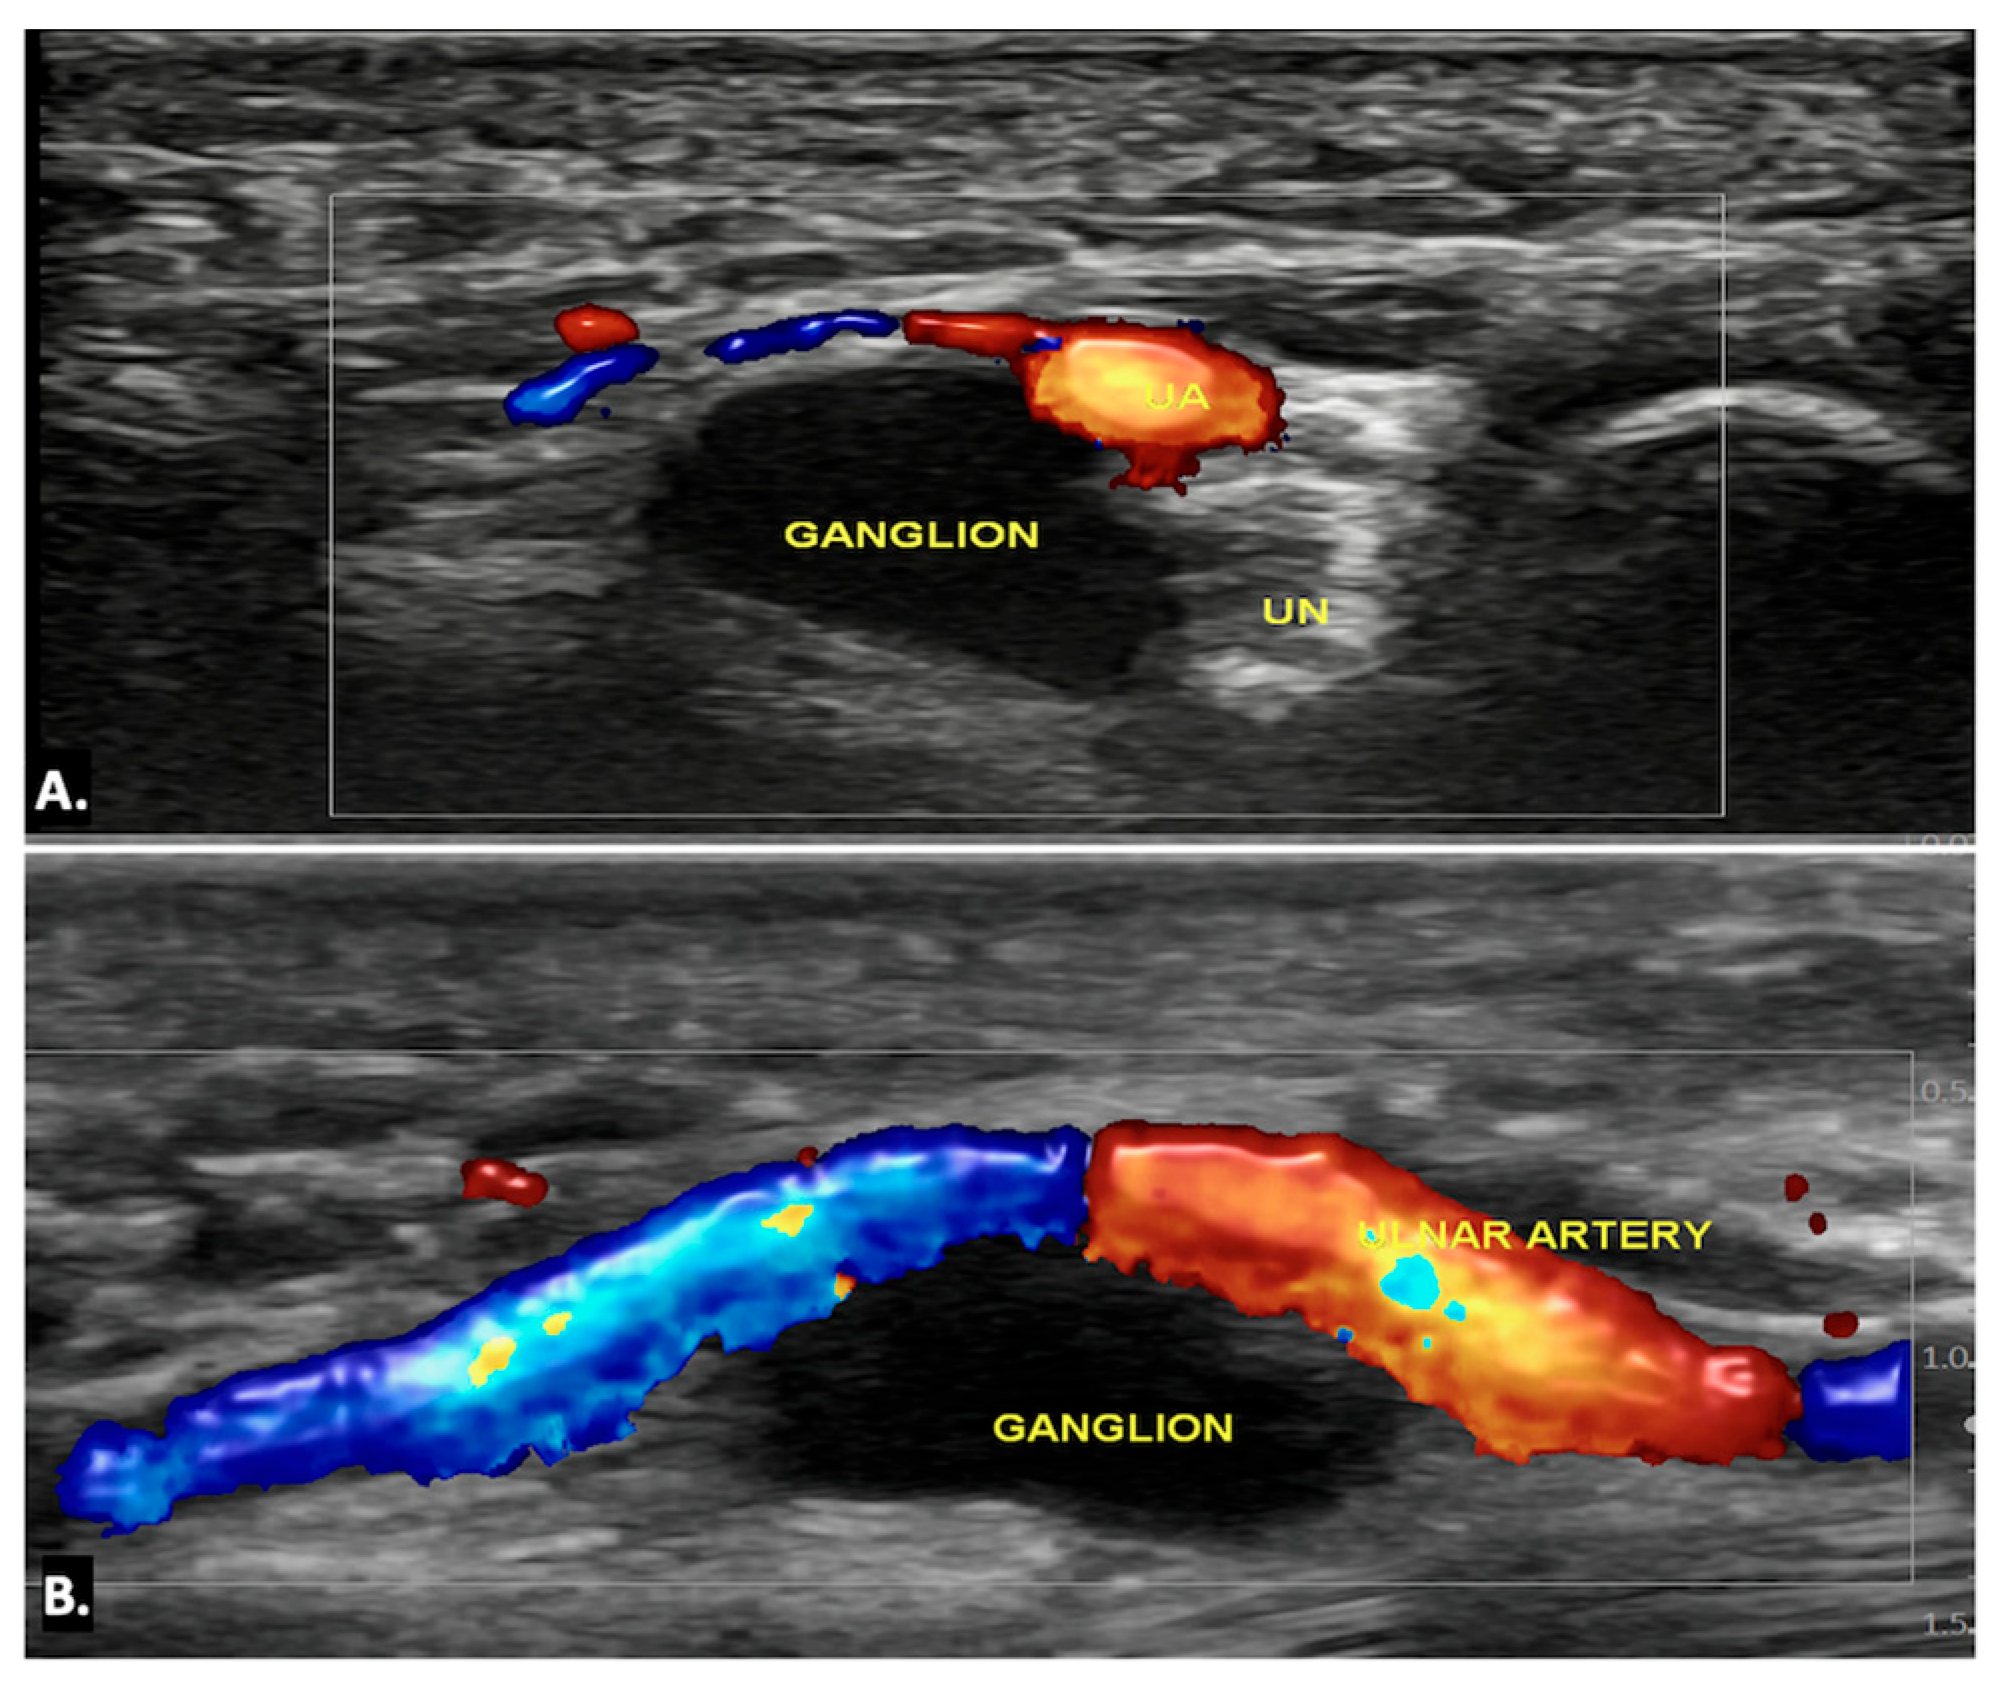

4.3. Ganglion Cysts

| Ganglion Cysts | A well-circumscribed anechoic or hypoechoic lesion with posterior acoustic enhancement. May show communication with joints or tendon sheaths. No internal vascularity on Doppler. | Well-defined, hypointense on T1 and hyperintense on T2-weighted images. Thin peripheral enhancement post-contrast. Possible nerve displacement/compression with T2 hyperintensity indicating oedema. |